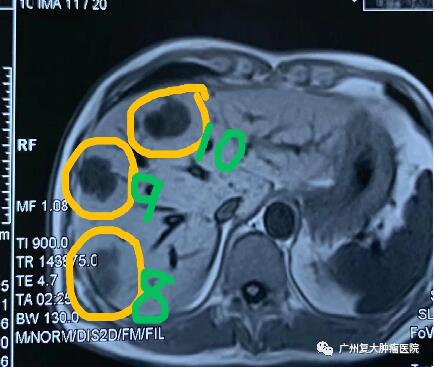

为求进一步诊疗,2020年11月,患者来广州复大肿瘤医院就诊。入院完善相关检查发现:CA-199指标高达2289u/ml(CA-199属胃肠道肿瘤相关抗原,是一种肿瘤标志物,正常值≤37u/ml);肝实质内有多个结节状,较大者约4.3×3.8cm。胰腺体、尾部均有肿块,并邻近肠管、脾静脉局部粘连不清,大小约4.3x3.3cm。

影像图片显示

图1